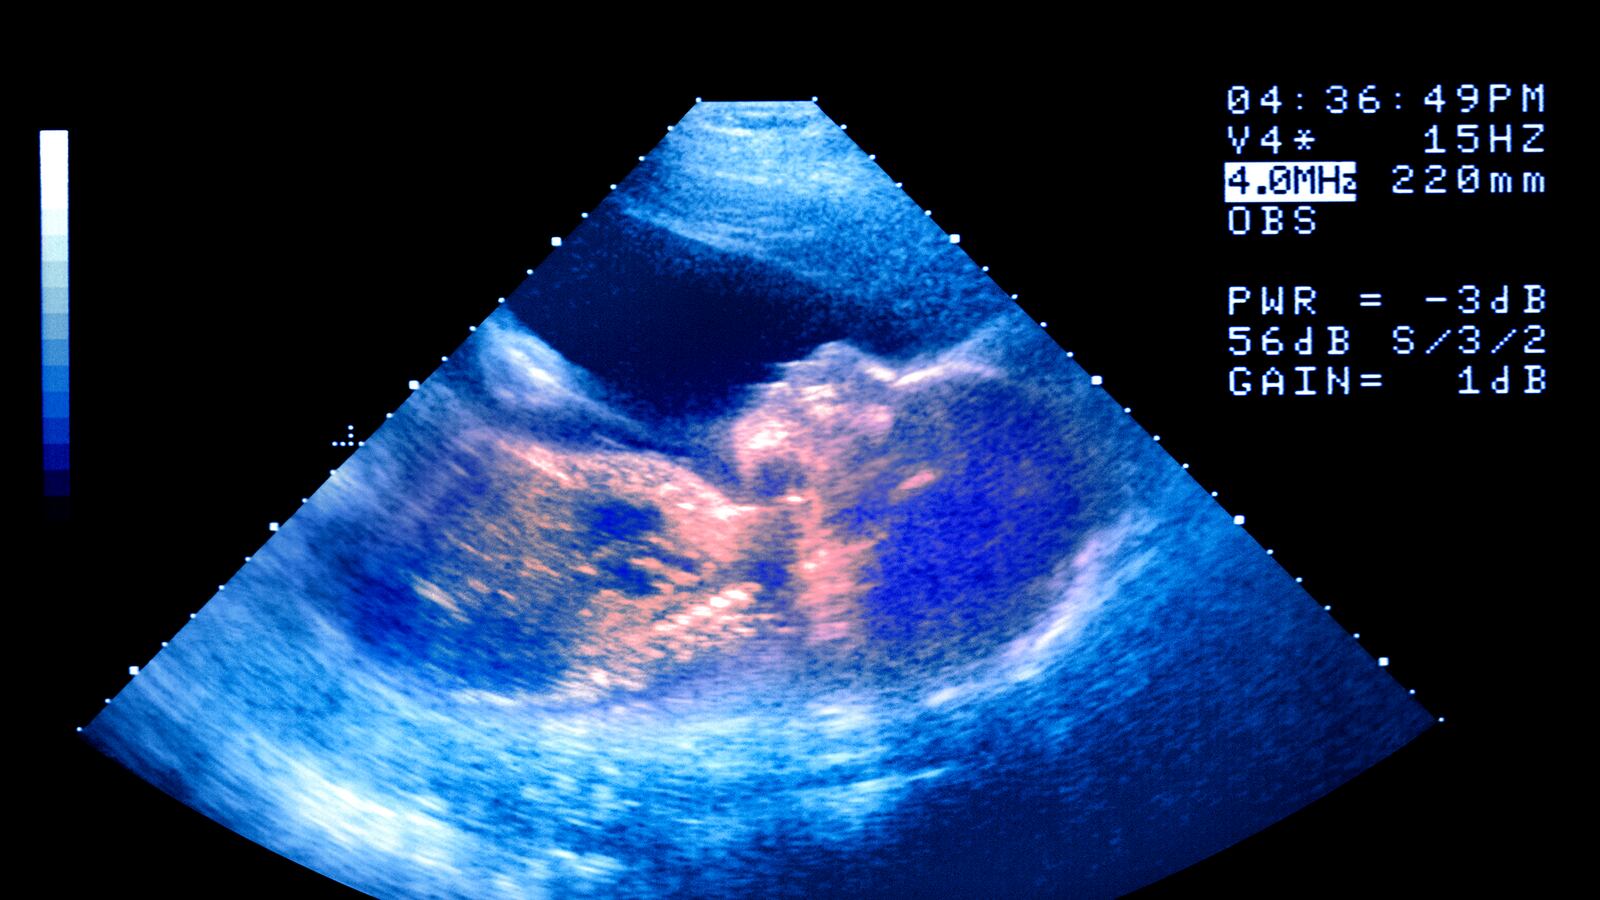

A new report from the Society of Associated Reproductive Technology out today reveals how pervassive in vitro fertilization (IVF) has become. In 2012, 61,740 babies conceived through reproductive technology were born in the U.S., 2,000 more than the previous year. Over 99 percent of those babies were conceived through in vitro fertilization (IVF). In total, over 1.5 percent of all births in 2012 were a result of IVF, an all-time high. More women are also using only single emrbyos to avoid multiple births. In 2007, just 4 percent of women under 35 used a single embryo for IVF, but it jumped to 15 percent in 2012.